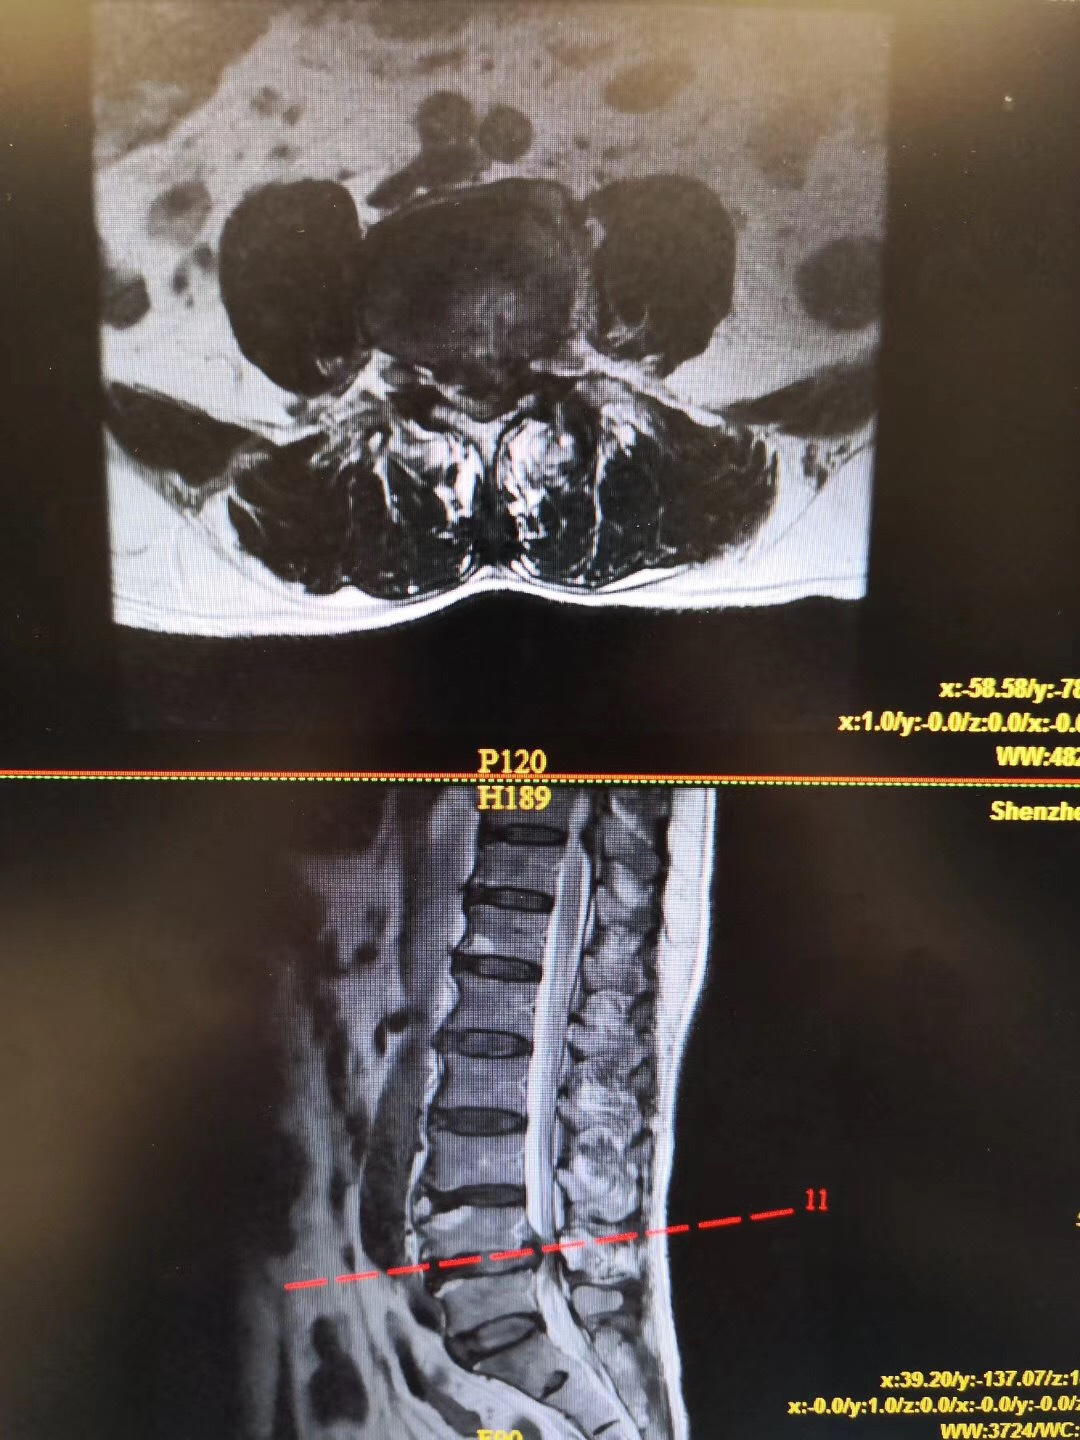

症状:双下肢麻痛伴间歇性跛行1年,行走100米即出现双下肢麻痛,严重影响生活。

诊断:腰椎间盘突出伴椎管狭窄症(L4/5节段),腰椎不稳定(L4/5节段),予施行“后路腰椎管减压固定融合术”治疗。